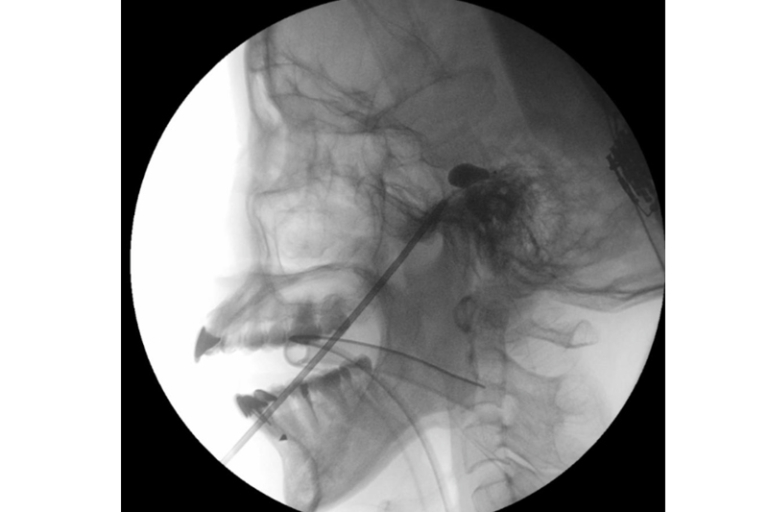

「經皮球囊壓迫術」屬微創介入技術,用於緩解與三叉神經相關的疼痛。而三叉神經負責面部感覺,當其功能異常時,會引發劇烈的面部疼痛。醫生會經面頰穿刺將微型球囊導管置入顱底的三叉神經節,用顯影劑擴張球囊,壓迫痛覺神經纖維。術中通過透視影像確認球囊呈梨形外觀以確保位置準確,從而精準阻斷痛覺傳導。